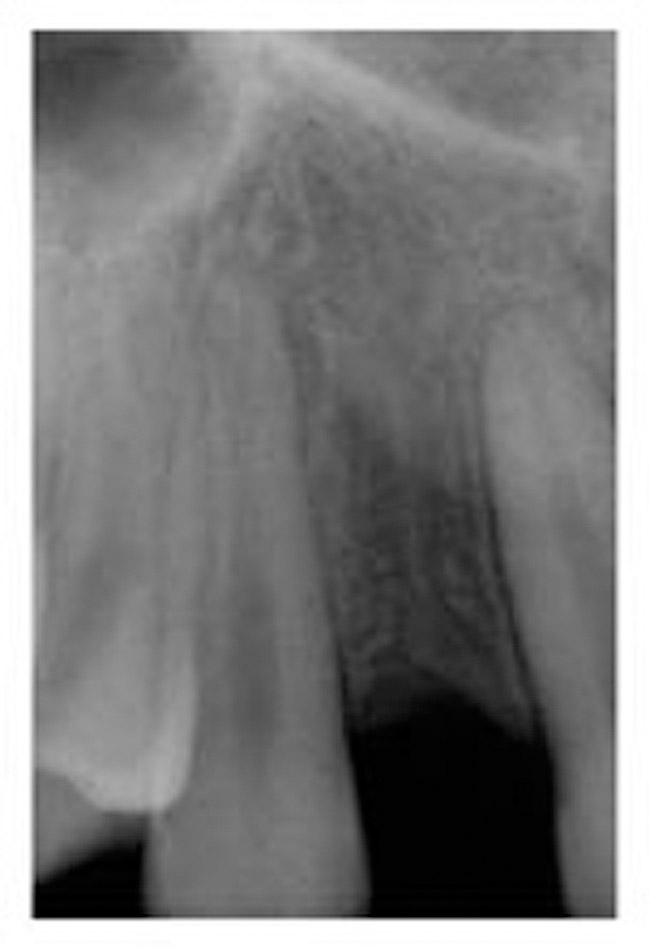

Figure 2  Pretreatment digital radiograph, right lateral incisor.

Figure 2

A 19-year-old non-smoking female presented for tooth replacement at the maxillary right and left lateral incisors, which were congenitally missing (Figure 1). The post-orthodontic result was adequate for the placement of 3-mm one-piece small-diameter implants. The preoperative radiographs can be seen in Figure 2 and Figure 3. The pretreatment clinical view in Figure 4 and Figure 5 shows the small intertooth space present in the lateral incisor areas. One of the most challenging tasks with congenitally missing lateral incisor cases is to create an acceptable soft tissue emergence profile from a crestal profile that is flat from the mesial of the canines to the distal of the centrals (Figure 4 and Figure 5). After pretreatment planning which consisted of a complete medical and dental history, radiographic analysis, and upper and lower study models mounted by a facebow transfer technique, the fabrication of a TempStent II surgical guide was completed. Figure 6 and Figure 7 show the occlusal view of the TempStent II guide on the study cast and in the oral cavity, respectively.